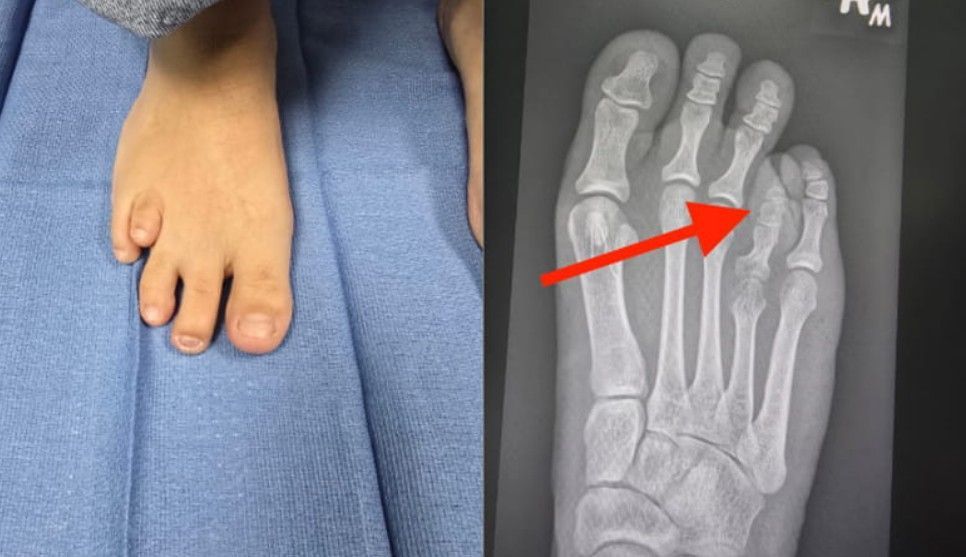

Geralmente, o dedo correspondente ao metatarso curto parece menor, mais retraído ou até "flutuante", sem o contato adequado com o solo. Isso acontece porque o osso que deveria empurrar o dedo para a frente não tem o comprimento esperado.

Na maioria dos casos, o osso mais afetado é o 4º metatarso (o que leva ao dedo anelar), mas a Braquimetatarsia pode ocorrer em qualquer um dos cinco metatarsos ou até mesmo em vários ao mesmo tempo.

- Isolada: Apenas um metatarso está encurtado.

- Radiografias (Raios-X): São essenciais. As radiografias fornecem imagens claras dos ossos do pé, permitindo ao médico medir o comprimento exato de cada metatarso e compará-los, confirmando o diagnóstico de Braquimetatarsia. Também ajudam a avaliar a angulação e o alinhamento dos ossos.

Alongamento Ósseo Gradual com Fixador Externo (distração osteogênica):

- Como funciona: Um aparelho externo é fixado ao metatarso encurtado. O paciente (ou familiar) ajusta o aparelho diariamente, alongando o osso milimetricamente ao longo de várias semanas.

- Processo: O corpo gera novo tecido ósseo no espaço criado, corrigindo o comprimento do metatarso de forma gradual.

- Vantagens: Minimiza o risco de complicações nervosas e de tecidos moles. O paciente participa ativamente do processo de alongamento.

- Desvantagens: O uso do fixador externo por algumas semanas pode ser incômodo, e a recuperação total leva mais tempo.